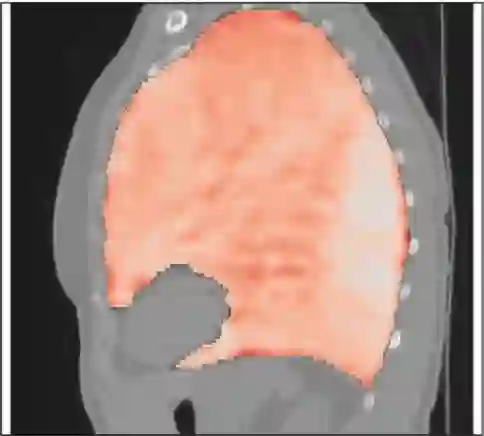

Deformable image registration is a fundamental task in medical image analysis and plays a crucial role in a wide range of clinical applications. Recently, deep learning-based approaches have been widely studied for deformable medical image registration and achieved promising results. However, existing deep learning image registration techniques do not theoretically guarantee topology-preserving transformations. This is a key property to preserve anatomical structures and achieve plausible transformations that can be used in real clinical settings. We propose a novel framework for deformable image registration. Firstly, we introduce a novel regulariser based on conformal-invariant properties in a nonlinear elasticity setting. Our regulariser enforces the deformation field to be smooth, invertible and orientation-preserving. More importantly, we strictly guarantee topology preservation yielding to a clinical meaningful registration. Secondly, we boost the performance of our regulariser through coordinate MLPs, where one can view the to-be-registered images as continuously differentiable entities. We demonstrate, through numerical and visual experiments, that our framework is able to outperform current techniques for image registration.